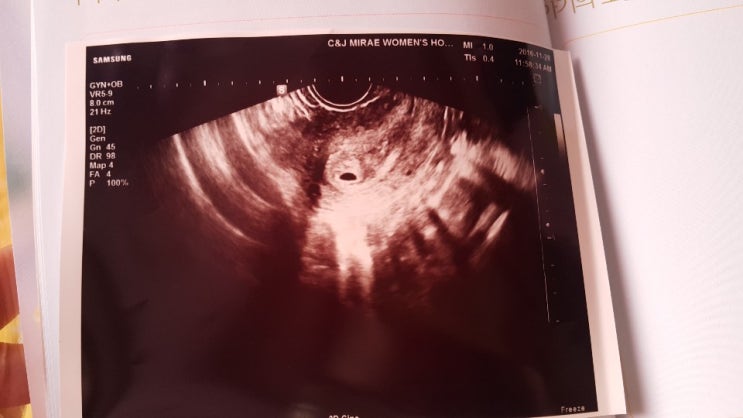

운뚱_ 첫 만남 그리고 연우

운뚱이와 운명적인 만남 운뚱이를 처음 만났을 때 난 정말 좋았어 행복했지.. ^^ 세상을 다 가진 기분이었...